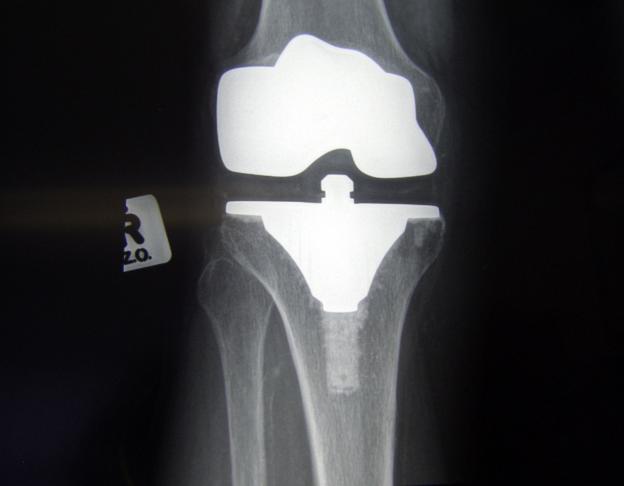

Личният лекар обикновено изпраща пациента за рентгенова снимка. Най-често става дума за заболяването гонартроза. Обстойните прегледи и диагностиката с апаратура могат да покажат най-точно какво се е случило и дали заболяването е начеващо, прогресиращо и дало ли е вече някакви макар и минимални изменения.

Истината е, че в преобладаващия процент от случаите се касае за износване на хрущялното покритие на капачката на коляното. Тя би трябвало да се движи точно в средата на хрущялен жлеб на бедрената кост. Капачката често опира повече по външния или по вътрешния борд на жлеба. Причината често се крие в периода на прохождането. Ако сме проходили твърде рано или сме карали лек рахит, или сме били поставени рано и дълго в проходилка, или сме наследили краката на дядо или прабаба, или съвкупност от две и повече причини от изброените по-горе, имаме голям шанс в първите години от живота си да сме с промени във формата на коленете. Те биха изглеждали като Х или О. Обикновено това кара капачката да опира по-силно във външния или вътрешния борд на жлеба. Това е и основната причина за ранното износване на хрущялното покритие между капачката и бедрената кост. Това са основните причини за развитие на гонартроза впоследствие, след 40-годишна възраст.

На пазара има изобилие от хрущяловъзстановяващи средства, но колкото и да смазваме два детайла, които се трият неправилно, това няма да помогне и ще носи само временен ефект. Най-добре е да се центрира капачката в жлеба и да се повдигне малко, за да се излекува лошото триене. Това обаче се прави от лекар специалист и в никакъв случай от чакръкчии. Те могат да ви навредят. Увреждането може да се отстрани пак от специалист с т.нар. извънставна процедура, не по-дълга от 30 минути, без да се прилага пълна анестезия.